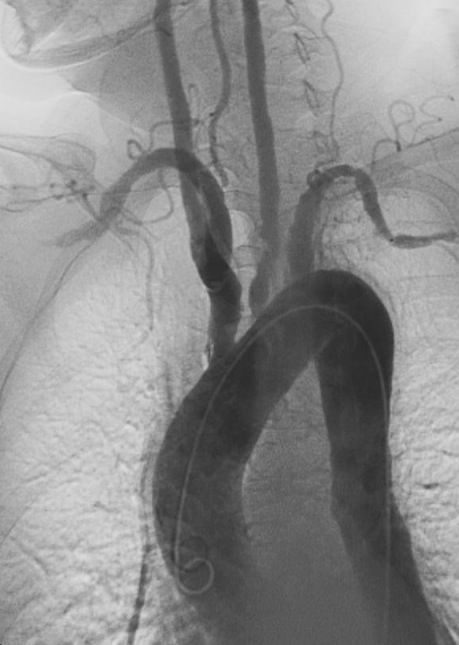

Takayasu arteritis is a granulomatous vasculitis of the aorta and its major branches. It primarily affects women and typically has its onset in early adulthood. Takayasu arteritis can present with nonspecific constitutional symptoms of malaise, fever, and weight loss or with manifestations of vascular damage (diminished pulses, unequal blood pressures in the arms, bruits over carotids, and subclavian arteries, limb claudication, and hypertension). There are no specific laboratory abnormalities; the ESR and the C-reactive protein level are elevated in most cases. The diagnosis is established by imaging studies, usually, MRI, which can detect inflammatory thickening of the walls of affected vessels, or CT angiography, which can provide images of the stenoses, occlusions, and dilations characteristic of arteritis. Corticosteroids (eg, oral prednisone) are the mainstay of treatment. The addition of methotrexate or mycophenolate mofetil to prednisone may be more effective than prednisone alone. Takayasu arteritis has chronic relapsing and remitting course that requires ongoing monitoring and adjustment of therapy.